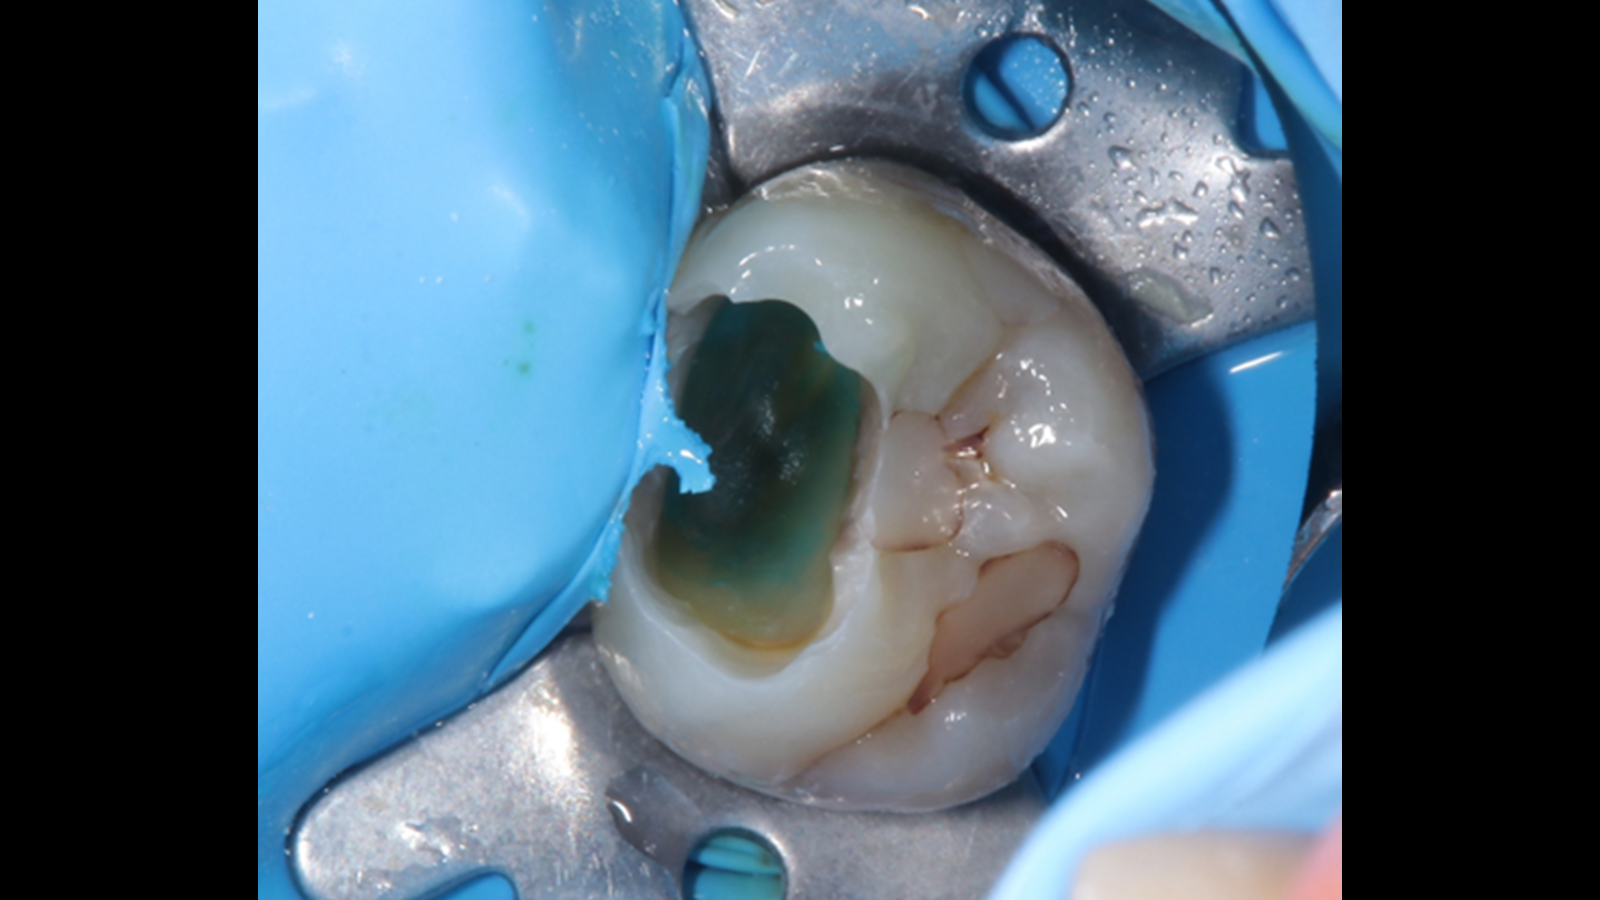

露出部の歯髄に対して部分断髄を行い、止血確認後にMTAセメントを用いた歯髄保護処置を行いました。

その後、セラミックよる直接修復を行い、処置後のデンタルX線写真にて封鎖状態を確認しました。